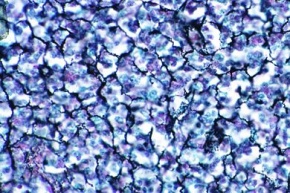

Mikropräparat - Mastzellen im Omentum der Ratte. Färbung mit Toluidinblau-Paracarmin

Mikropräparat - Mastzellen im Omentum der Ratte. Färbung mit Toluidinblau-Paracarmin